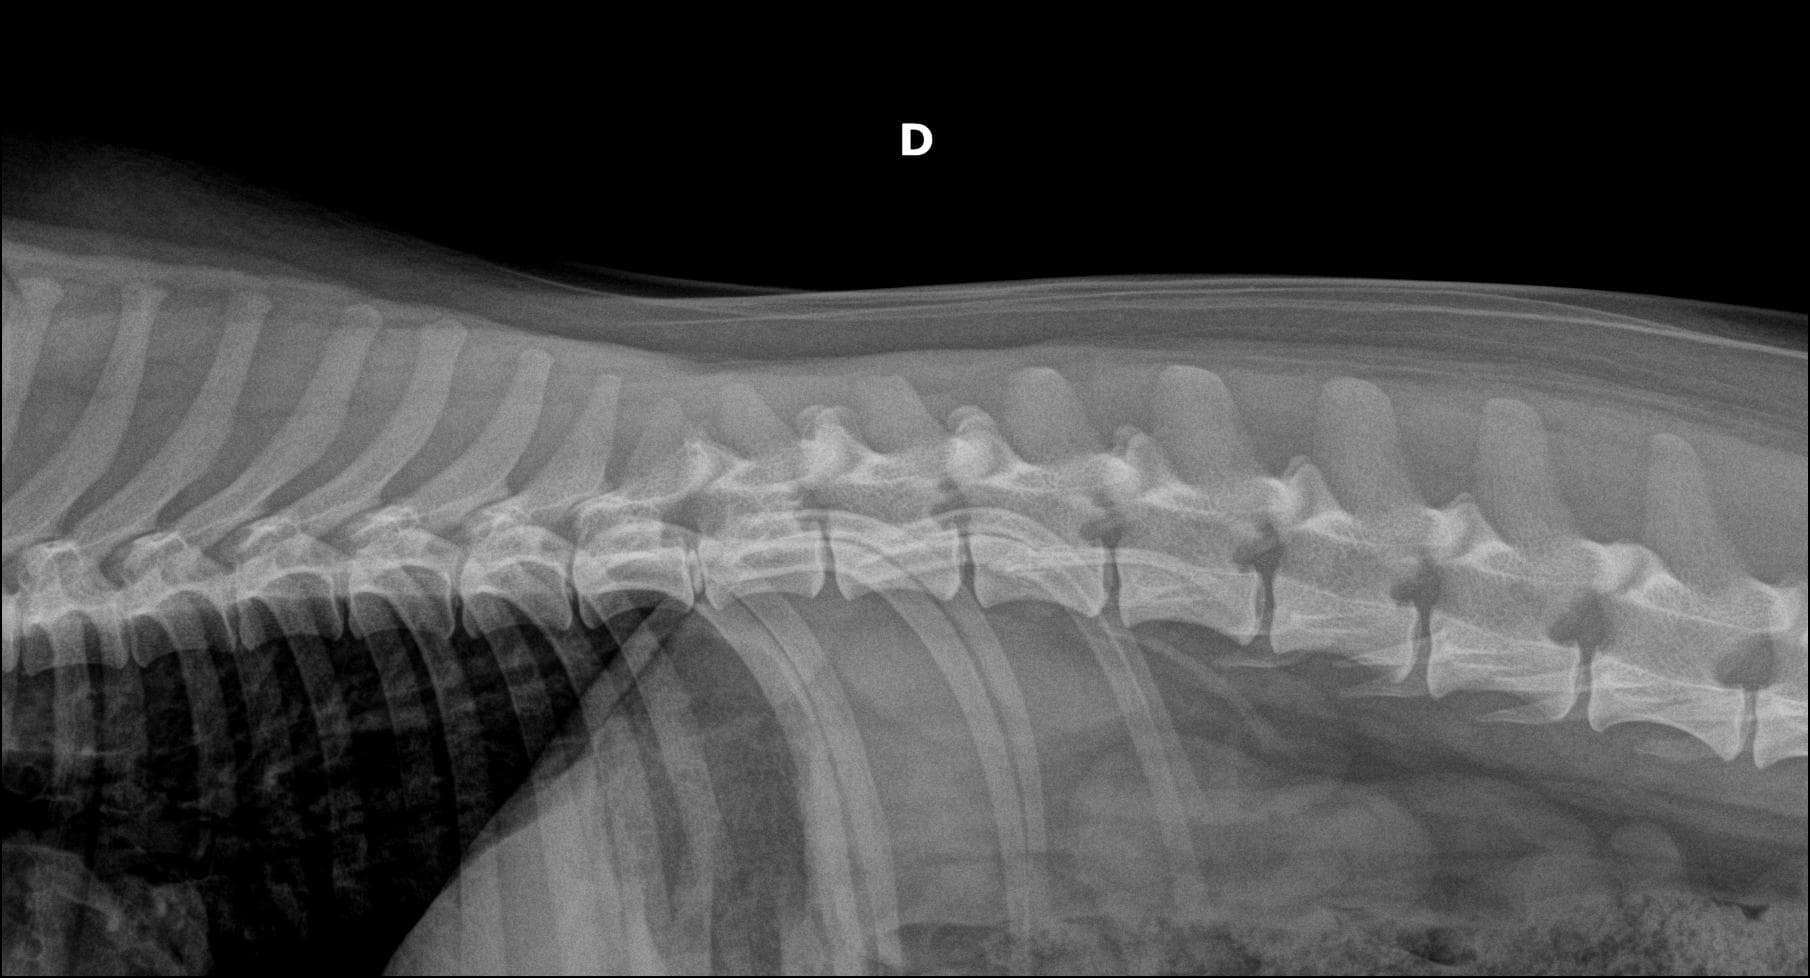

Nosso serviço de radiologia digital é projetado para oferecer diagnósticos precisos para cuidar da saúde dos pets. Contamos com equipamentos de última geração que nos permitem capturar imagens de alta qualidade e definição, fornecendo uma visão clara das estruturas. Essa tecnologia avançada nos permite identificar diversas condições médicas com maior precisão e detalhamento.